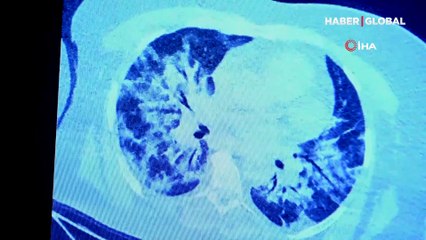

pTokat'ta korona virüs tedavisi gören Beyzanur Akgül (22), yaşadıklarını hastane penceresinden dile getirerek sağlıklı kişileri daha duyarlı olmaya davet etti. p br p Yaşadıklarını bana bir şey olmaz deyip korunma önlemi almayan vatandaşlar için adeta ders niteliğinde. İşte genç kızın yaşadıkları: “Devletimiz var olsun. Hastane çalışanlarımız sağlıkçılarımız gerçekten çok ilgi gösteriyorlar. Bu da bizim için bir moral kaynağı. Rabbim onlardan da razı olsun" dedi. "Bu psikolojiyi kimsenin yaşamasının istemem" Hastalığı atlatacağına inandığını ifade eden Akgül, "Ama anneme, babama veya başkasına bulaştırabilecek olma korkusu beni daha çok yıpratıyor. Bu psikolojiyi kimsenin yaşamasının istemem. Ben hep hayattan tat alamıyorum diye hayıflanırdım. 9 gündür hiçbir şeyin tadını ve kokusunu alamıyorum. Yaşam kalitem çok düştü. Bütün bunları yaşarken yalnız başımayım. Ben yaşıtlarıma şunu söylemek isterim. Maske estetik görünmüyor, bu sıcak havalarda bunaltıyor olabilir. Ama emin olun 14 gün boyunca sevdiklerinizden uzak, tek başınıza yalnız bir oda da tek başınıza vakit geçirmekten çok daha iyidir. O nedenle maske takın. Sevdiklerinizden uzak kalmak gerçekten çok kötü. Yaşamanızı istemem" diye konuştu. "Bugün benim yerime içlerine güzel kokular çeksinler" Duygu dolu konuşmasında tat almadığını belirten Akgül, kendisini izleyecek olanlardan bir ricada bulunarak, "Bizi izleyecek olanlara seslenmek istiyorum. Bu tat ve koku alamama gerçekten benim yaşam kalitemi ciddi manada düşürdü. Benim onlardan küçük bir ricam var. Bugün benim yerime içlerine güzel kokular çeksinler. Domatesi, salatalığı koklasınlar, havayı, çiçekleri koklasınlar. Bugün yine benim yerime rabbimin verdiği nimetleri tatsınlar. Tat alabildiklerine şükretsinler. Maske taksınlar sağlıkla sevdiklerinin yanında kalsınlar" ifadelerini kullandı. "Nefes alamıyormuş gibi hissediyor çırpınıyorum" 9 gündür hastalıkla mücadele etmeye devam ettiğinin altını çizen Akgül, açıklamalarını şöyle tamamladı: "Bugün 5. günüm ama bende 9 gündür belirtiler var. Tat ve koku alma duyusu yok, baş ağrısı var. Arda bir öksürük geliyor. Öksürürken psikolojik olarak yaşadığımı sanıyorum, nefes alamıyormuş gibi hissediyor çırpınıyorum. Bunlara yalnız başıma göğüs geriyorum. O nedenle tedbiri elden bırakmamak gerek.